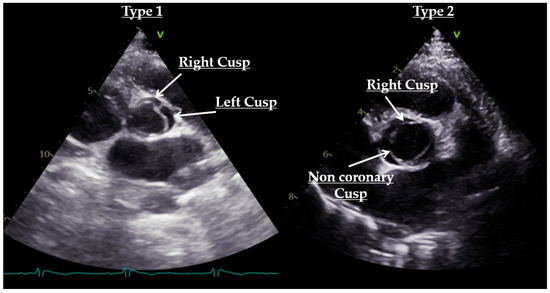

- Sievers, H.H.; Schmidtke, C. A classification system for the bicuspid aortic valve from 304 surgical specimens. J. Thorac. Cardiovasc. Surg. 2007, 133, 1226–1233. [Google Scholar] [CrossRef]